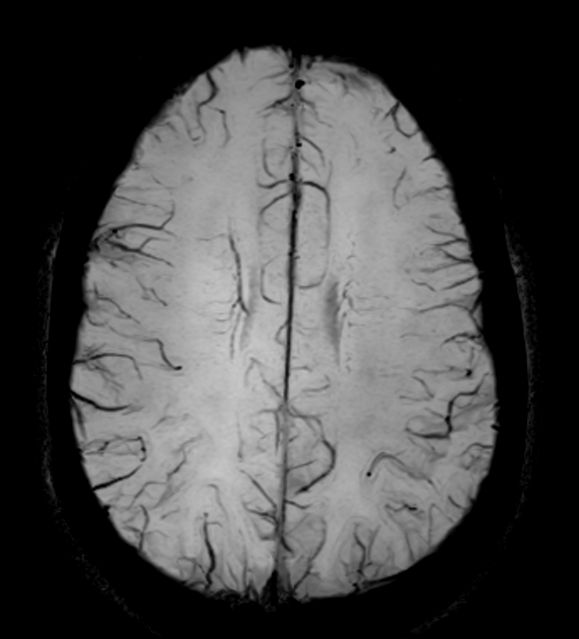

Axial SWIp (minIP)

-